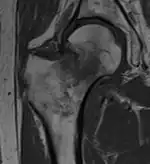

Diagnosis of trabecular edema is primarily done via magnetic resonance imaging (MRI). The presence of edema within the bone marrow yields a visible signal on the MRI, due to displacement of the normally fatty tissue within the marrow by interstitial fluid with higher water content; this change in composition is then reflected by the MRI due to differences in the T1-weighted and T2-weighted images.[5][1]

A healthy bone is rich in fat and has lower water content, therefore it appears as bright signals on T1-weighted images and dark on T2-weighted images.[2] Conversely, regions with trabecular edema has lower fat and higher water content. Hence, they have a comparatively lower intensity than normal bone tissues on a T1-weighted image, and a higher intensity on a T2-weighted image.[42]